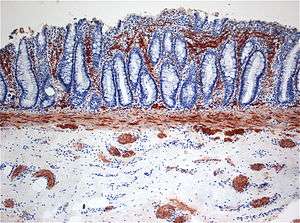

| Histopathology of Hirschsprung disease. Enzyme histochemistry showing aberrant acetylcholine esterase (AchE)-positive nerve fibers (brown) in the lamina propria mucosae. | |

Hirschsprung's disease (HD) is a form of megacolon that occurs when part or all of the large intestine or antecedent parts of the gastrointestinal tract have no ganglion cells and therefore cannot function. During normal prenatal development, cells from the neural crest migrate into the large intestine (colon) to form the networks of nerves called the myenteric plexus (Auerbach plexus) (between the smooth muscle layers of the gastrointestinal tract wall) and the submucosal plexus (Meissner plexus) (within the submucosa of the gastrointestinal tract wall). In Hirschsprung's disease, the migration is not complete and part of the colon lacks these nerve bodies that regulate the activity of the colon. The affected segment of the colon cannot relax and pass stool through the colon, creating an obstruction.[1] In most affected people, the disorder affects the part of the colon that is nearest the anus. In rare cases, the lack of nerve bodies involves more of the colon. In five percent of cases, the entire colon is affected. The stomach and esophagus may be affected too.

The most accepted theory of the cause of Hirschsprung is that there is a defect in the craniocaudal migration of neuroblasts originating from the neural crest that occurs during the first 12 weeks of gestation. Defects in the differentiation of neuroblasts into ganglion cells and accelerated ganglion cell destruction within the intestine may also contribute to the disorder.[4]

This lack of ganglion cells in the myenteric and submucosal plexus is well-documented in Hirschsprung's disease.[3] With Hirschsprung's disease, the segment lacking neurons (aganglionic) becomes constricted, causing the normal, proximal section of bowel to become distended with feces. This narrowing of the distal colon and the failure of relaxation in the aganglionic segment are thought to be caused by the lack of neurons containing nitric oxide synthase.[3]

Definitive diagnosis is made by suction biopsy of the distally narrowed segment.[12] A histologic examination of the tissue would show a lack of ganglionic nerve cells. Diagnostic techniques involve anorectal manometry,[13] barium enema, and rectal biopsy. The suction rectal biopsy is considered the current international gold standard in the diagnosis of Hirschsprung's disease.[14]